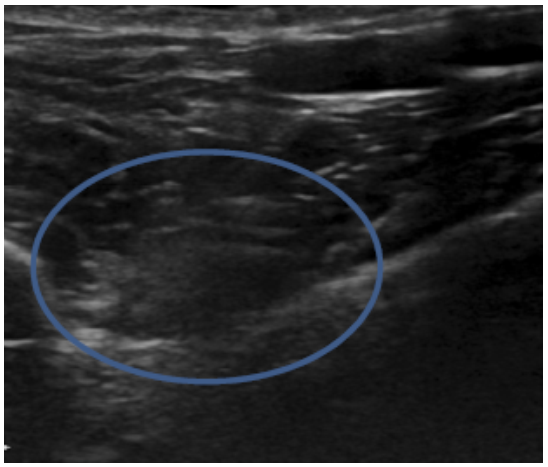

Methods: Medical records of 73 agility performance canines that underwent musculoskeletal ultrasound evaluation of bilateral iliopsoas muscle groups were retrospectively reviewed. Data included signalment, previous radiographic findings, and ultrasound findings. A 3-tier grading scheme for acute strains was used while the practitioner also evaluated for evidence of chronic injury and bursitis.

Results: The majority of pathologies were localised to the tendon of insertion, with the majority being low grade I-II strains (80.8%). Tendon fibre disruption (71.2%) and indistinct hypoechoic lesions (91.8%) were the most common of acute changes noted. Hyperechoic chronic changes were noted in 84.9 percent of cases. Acute and chronic changes were commonly seen together (62.8%).

Conclusion: Diagnostic musculoskeletal ultrasound was used to identify lesions of the iliopsoas tendon consistent with acute and chronic injury, as well as identifying the region of pathology. The majority of agility performance dogs had low grade acute strains based on the tiered system, with mixed acute and chronic lesions being noted frequently.

Application: Diagnostic musculoskeletal ultrasound provides a non-invasive diagnostic modality for patients suspected of having an iliopsoas strain.